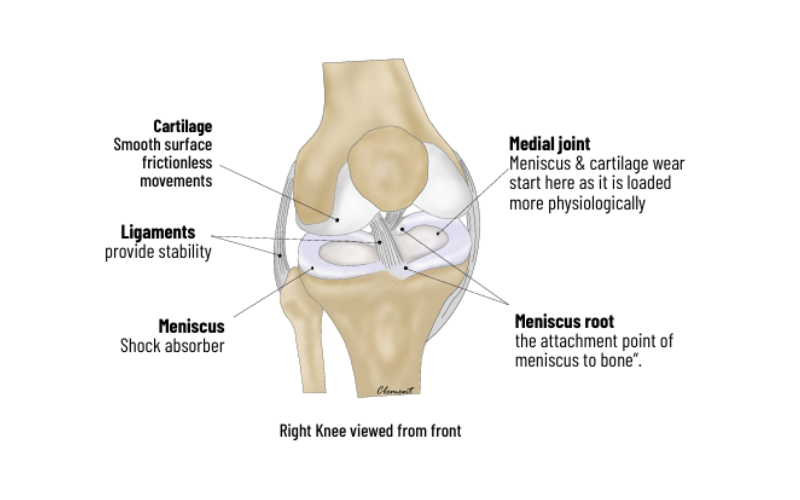

The knee joint is formed by Femur (thigh bone), tibia (leg bone) and patella Damage to the joint is called arthritis and is caused by Obesity, Meniscus tears, Malalignment (“bow-leg”) deformity overloading one compartment, instability (ligament tears) and rheumatological disorders.

Knee joint surface is covered by Hyaline Cartilage, which is responsible for smooth and frictionless movements. When injured it does not heal due to lack of blood supply. Repair techniques include – MICROFRACTURE (bone marrow stimulation with drilling) suitable for small lesions, OATS, in which cylindrical plugs of cartilage from non-weight bearing areas are transferred to thedefects and Cell based techniques in which concentrated stem cells from bone marrow (BMAC) or patient’s own cartilage cells (ACI) grown in a lab are used to fill the defect.